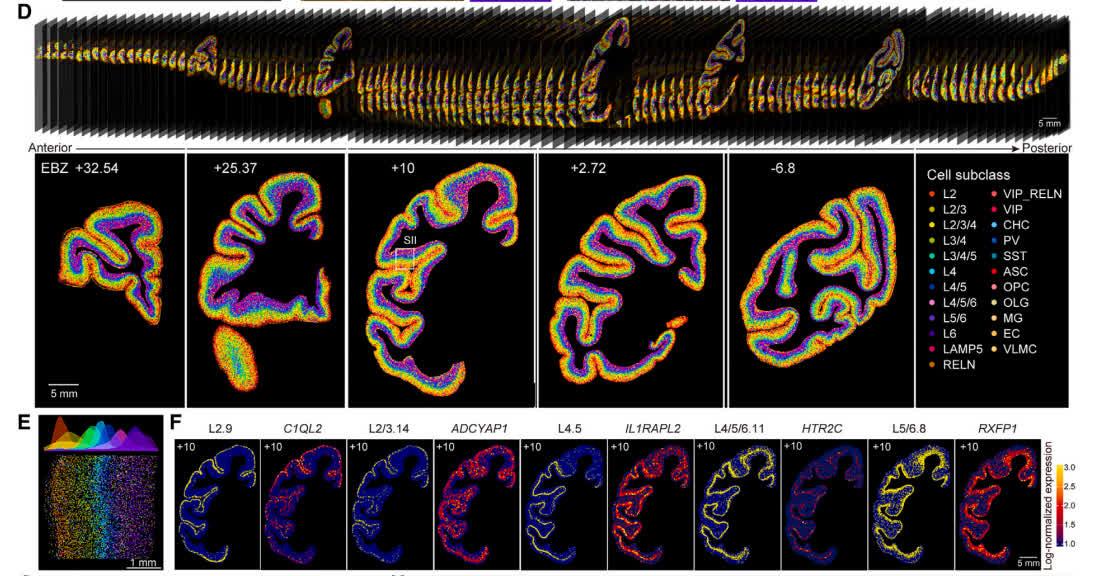

獼猴大腦皮層細胞類型空間分布圖譜 在研究中,研究人員通過華大時空組學技術Stereo-seq,採集了獼猴大腦161張厚度為10微米切片的空間轉錄組數據,並結合華大自主研發的另一項技術——高通量單細胞核轉錄組測序技術DNBelab C4 snRNA-seq,獲取了百萬級別的獼猴大腦皮層單細胞核轉錄組數據。同時,通過對獼猴大腦皮層的143個腦區中單個細胞的基因表達及狀態、空間信息進行聯合分析,研究團隊繪製了全球首個食蟹猴大腦全皮層的三維單細胞圖譜,並且繪製了細胞類型分類樹,揭示了不同類型細胞與腦區層級結構的關係。 研究團隊發現,獼猴大腦中大量興奮性神經元、抑制性神經元以及非神經元細胞在大腦皮層中的分布呈現明顯的各層面及各腦區的特異性。研究團隊又以視覺系統和軀體感覺系統為例,展開進一步研究,發現兩個系統的細胞類型組成與腦區層級組織之間存在顯著的相關性,處於相同層級的腦區往往具有類似的細胞類型組成,揭示了細胞組成和腦區結構之間的關係。 “獼猴腦細胞圖譜的繪製,將幫助我們更好地認識腦疾病,為未來設計疾病治療靶點提供基礎參考資源。”文章共同通訊作者、華大生命科學研究院院長徐訊認為,“它將有望推動腦科學領域的突破性進展,如在類腦智能和腦機接口中,通過更精確的腦電信號採集,實現更複雜的機體活動”。 中國科學院腦智卓越中心學術主任蒲慕明院士表示,未來,團隊將繼續在腦疾病機制與靶點研發、腦細胞與腦結構演化、腦功能的細胞分子機制等領域繼續攻關,推動中國在相關領域持續產生原創性、引領性成果。 本次研究由多家單位的100多位跨學科、跨領域的研究人員合作,依託我國自主研發的核心技術與大平台,以“大科學”科研攻關模式共同完成。研究產生了較為完整的全球首套獼猴全腦皮層的單細胞以及空間轉錄組數據,目前,數據資源庫現已實現公開共享。